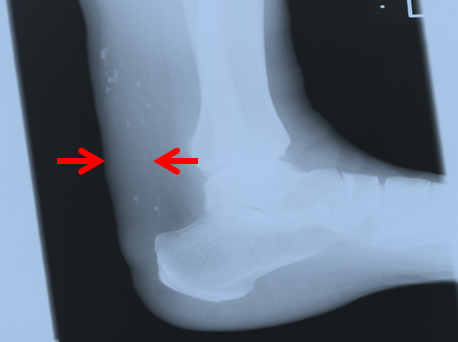

一部の患者さんでは、多くはありませんが、手の甲・膝(ひざ)・肘(ひじ)・瞼(まぶた)などにコレステロールが沈着して黄色っぽい隆起(皮膚黄色種)がみられます(図1:上段左右)。また、指摘されないと気付きにくいものの、頻度の高いものにアキレス腱へのコレステロール沈着によって生じるアキレス腱肥厚があります(図1:下段左右)。

診断には、LDLコレステロールの測定をはじめ、家系内調査、アキレス腱の厚さの評価が役立ちます。この

アキレス腱肥厚の検出は簡便かつ有用です。慣れた医師なら、触診(指でアキレス腱をつまむ)だけである程度予測できますし、検査も軟線X線撮影(男性8.0mm以上、女性7.5mm以上)、あるいは超音波(男性6.0mm以上、女性5.5mm)程度で済みます(図1:下段右)。

図1.FHにおける黄色腫とアキレス腱肥厚[50歳 男性、軟線X線検査でアキレス腱(矢印間)は21mm]